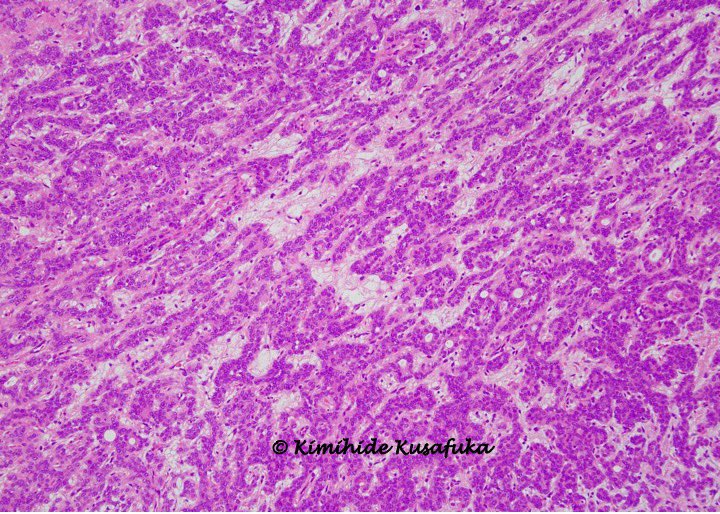

Гиперплазия это гистология

Гиперплазия это гистология 113 фотографий